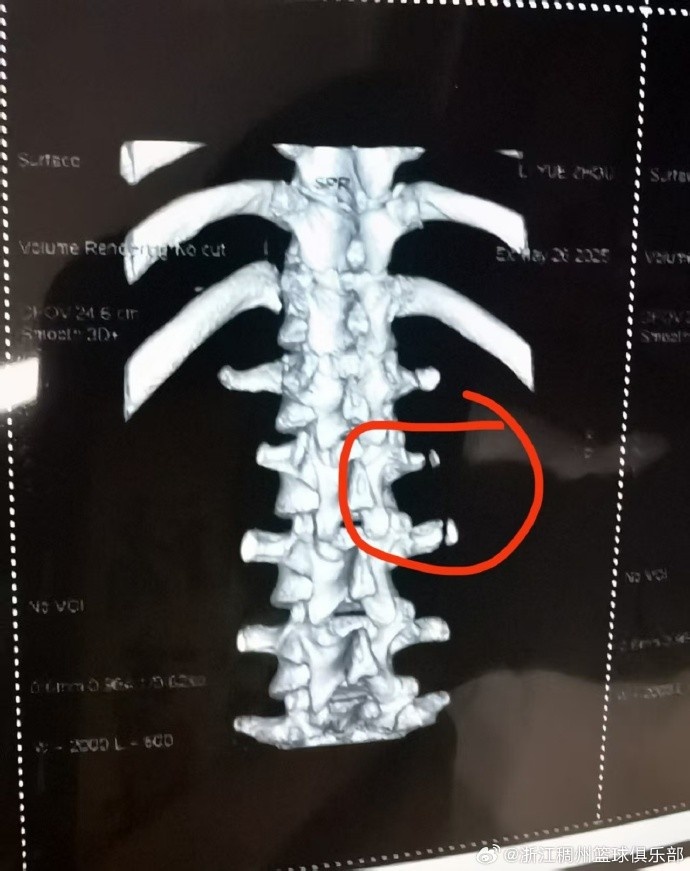

6月9日讯 浙江男篮官方宣布,李悦洲遭遇横突骨折,预计伤停3个月。

伤情通报| 我俱乐部球员李悦洲在5月26日秦皇岛备战U19世青赛训练中不幸遭遇横突骨折,经中国篮协联系北京积水潭医院骨科专家会诊,预计伤停3个月。